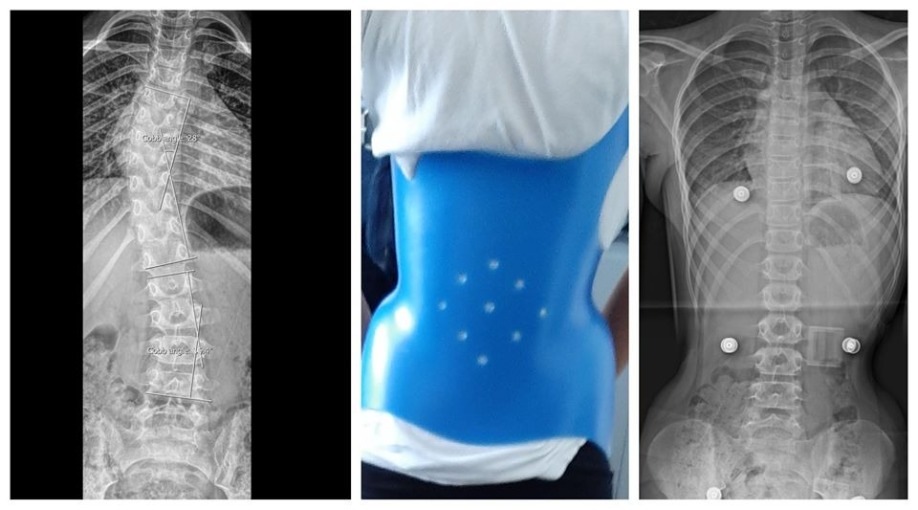

Idiopathic scoliosis is a sideways curvature of the spine of unknown aetiology which most commonly presents during puberty. It is much more common in girls compared to boys. Scoliosis is diagnosed with specific X-rays which allow the measurement of a specific angle (Cobb’s angle). Scoliosis is diagnosed when Cobb’s angle is more than 10 degrees. Scientific evidence suggests that the use of a brace in immature patients with a scoliosis of more than 25 degrees can prevent deformity deterioration and the need for surgical intervention.

The pictures below shows a patient of Dr. Zenios with more than 25 degrees of scoliosis (Cobb's angle). Our spinal brace for idiopathic scoliosis was applied with excellent results.